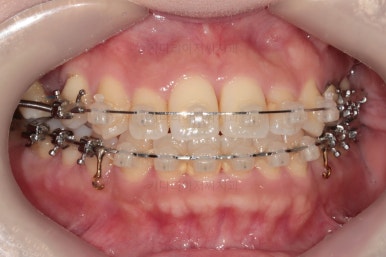

초진 시, 입안의 모습이에요.

결손부위가 눈에 띄고요.

결손부위가 양쪽에 있다보니 윗니 중간에 틈새가 벌어졌네요.

뒤쪽의 빈공간으로 치아들이 도미노처럼 쓰러져서 그렇습니다.

앞니의 약간의 틈새, 약간의 삐뚤어짐, 약간의 중앙선 틀어짐 등 심하진 않으나 약간씩의 문제점들이 있네요.

환자분이 선택하신 장치는 데이몬 클리어라고 하는 자가결찰 세라믹 장치입니다.

자가결찰 세라믹 중에 가장 심미적으로 우수한 장치가 데이몬 클리어인데요.

철사를 제외한 모든 파트가 세라믹으로 되어있습니다.

장치를 부착한 모습 참고해 주시고요.

아랫니는 중앙선을 맞추기 위해서 미니스크류를 이용해 한 쪽으로 당기는 중이고요.

이 과정에서 아랫니들이 약간은 뒤로 들어가져서 아랫입술 부위의 돌출감을 아주 약간은 줄일 수 있습니다.

윗니 임플란트 할 자리는 적절히 계속 맞춰줍니다.

중앙선도 점점 맞아지고 있어요.